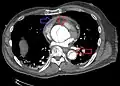

| Stanford type B dissection of the descending part of the aorta (3), which starts from the left subclavian artery and extends to the abdominal aorta (4). The ascending aorta (1) and aortic arch (2) shown in the image are not involved in this condition. | |